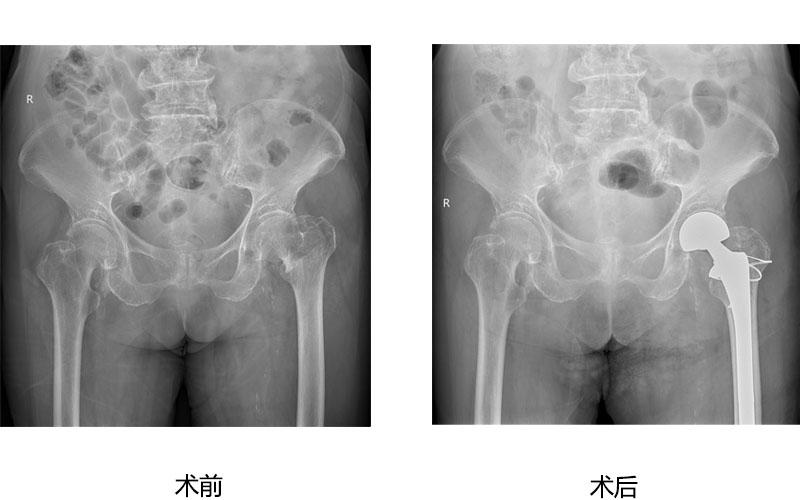

人工关节置换

人工关节置换为广大高龄老年股骨颈骨折、股骨粗隆间骨折病人提供快速康复治疗,为严重股骨头坏死、膝关节炎病人解除病痛,恢复正常行走功能。 病例展示如下:

股骨头坏死微创全髋人工关节置换术